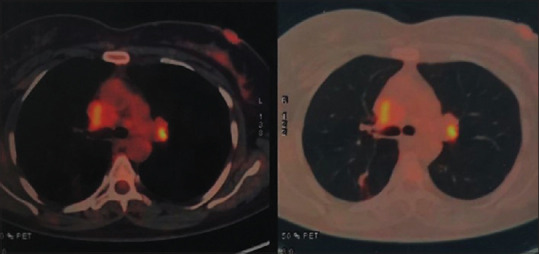

组织胞浆菌病表现为纤维化性纵隔炎和上腔静脉阻塞。

Histoplasmosis presenting as fibrosing mediastinitis and superior vena cava obstruction.